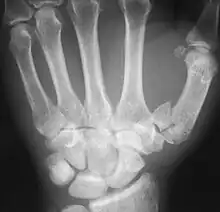

An X-ray showing a comminuted metacarpal bone fracture

- (medicine) To cause fragmentation (of bone).

- For example, comminuting fractures on ribs 4–8 along the rib angle most likely are associated to shots through the scapula, whereas injuries through or near to the costochondral articulation of the first rib could also be associated to wounds of the sternum or clavicle.

- In the past, there have been controversies over the use of bone graft in comminuted fractures of the forearm.

- When using reduction forceps, care must be taken to prevent comminuting the medial epicondylar fragment.